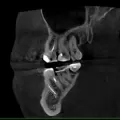

• К сожалению, данный снимок недостаточно качественный, чтоб было принято решение об удалении. В ряде случаев возможно перелечивание зуба, с последующим протезированием. Однозначно судить можно исходя из трехмерного снимка и клинического осмотра полости рта.

• Для принятия решения об удалении, необходимо оценить полный трехмерный снимок, во всех плоскостях. Но, определённо, эти конструкции следует снять, пролечить весь кариес и решить по КЛКТ. По поводу шестых зубов: 26-й зуб, с кистой подлежит удалению, 16-й зуб требует более детального осмотра.